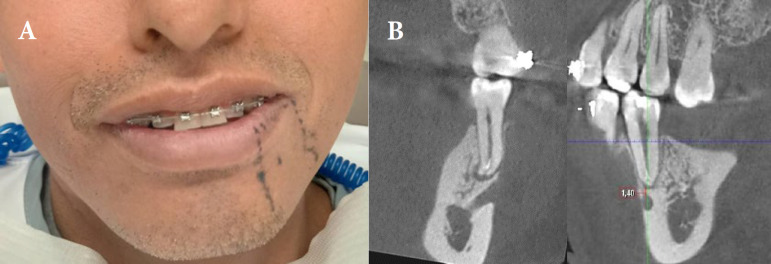

感觉异常被描述为由神经损伤引起的灼烧或刺痛感或部分麻木。感觉丧失可能是可逆性和/或不可逆性神经损伤的结果,可由局部或全身因素引起。局部因素包括埋伏牙造成的外伤性损伤、局部注射、牙髓治疗、种植体放置和接触有毒物质。本文报告一例麻醉注射后的感觉异常。一名44岁男子报告咀嚼和受寒时有中度疼痛。经临床检查,牙断裂线延伸在下颌左第二前磨牙冠中远端,用16倍显微镜观察。诊断为牙裂综合征,行根管治疗。第一次预约后,患者报告左侧下颌骨感觉改变,麻木和电击感,因此被诊断为精神神经感觉异常。双氯芬酸钠、硫胺素、氰钴胺、吡哆醇治疗7天,完成根管治疗和修复治疗。随访时间分别为1、3、6、8个月。第一个月后,感觉异常的感觉仍然存在,病人正在经历痛苦的“电击”。在8个月的随访中,感觉异常消失,感觉恢复正常。

Paresthesia is described as a burning or prickling sensation or partial numbness caused by neurologic injury. The sensory loss may be the result of a reversible and/or irreversible nerve damage, and it can be caused by local or systemic factors. Local factors include traumatic injuries caused by impacted teeth, local injection, endodontic therapy, implant placement and exposure to toxic materials. This article reports a paresthesia by anesthetic injection. A 44-year-old man reported moderate pain during chewing and exposure to cold. Upon clinical examination, extension of the tooth fracture line was in the mesiodistal region of the mandibular left second premolar crown and was detected with 16× magnification of microscope. The diagnosis was cracked tooth syndrome, and root canal treatment was indicated. After the first appointment the patient reported altered sensation on left side of mandible, numbness and electric shock sensation, and therefore was diagnosed with mental nerve paresthesia. Diclofenac sodium, thiamine, cyanocobalamin, and pyridoxine were prescribed for 7 days as part of the treatment, and then root canal and restorative treatments were completed. Patient was scheduled for follow-up appointments after 1, 3, 6, and 8 months. After the first month, the feeling of paresthesia was still present and the patient was experiencing a painful "electric shock". At the 8-month follow-up visit, the paresthesia had been resolved with return of normal sensation.